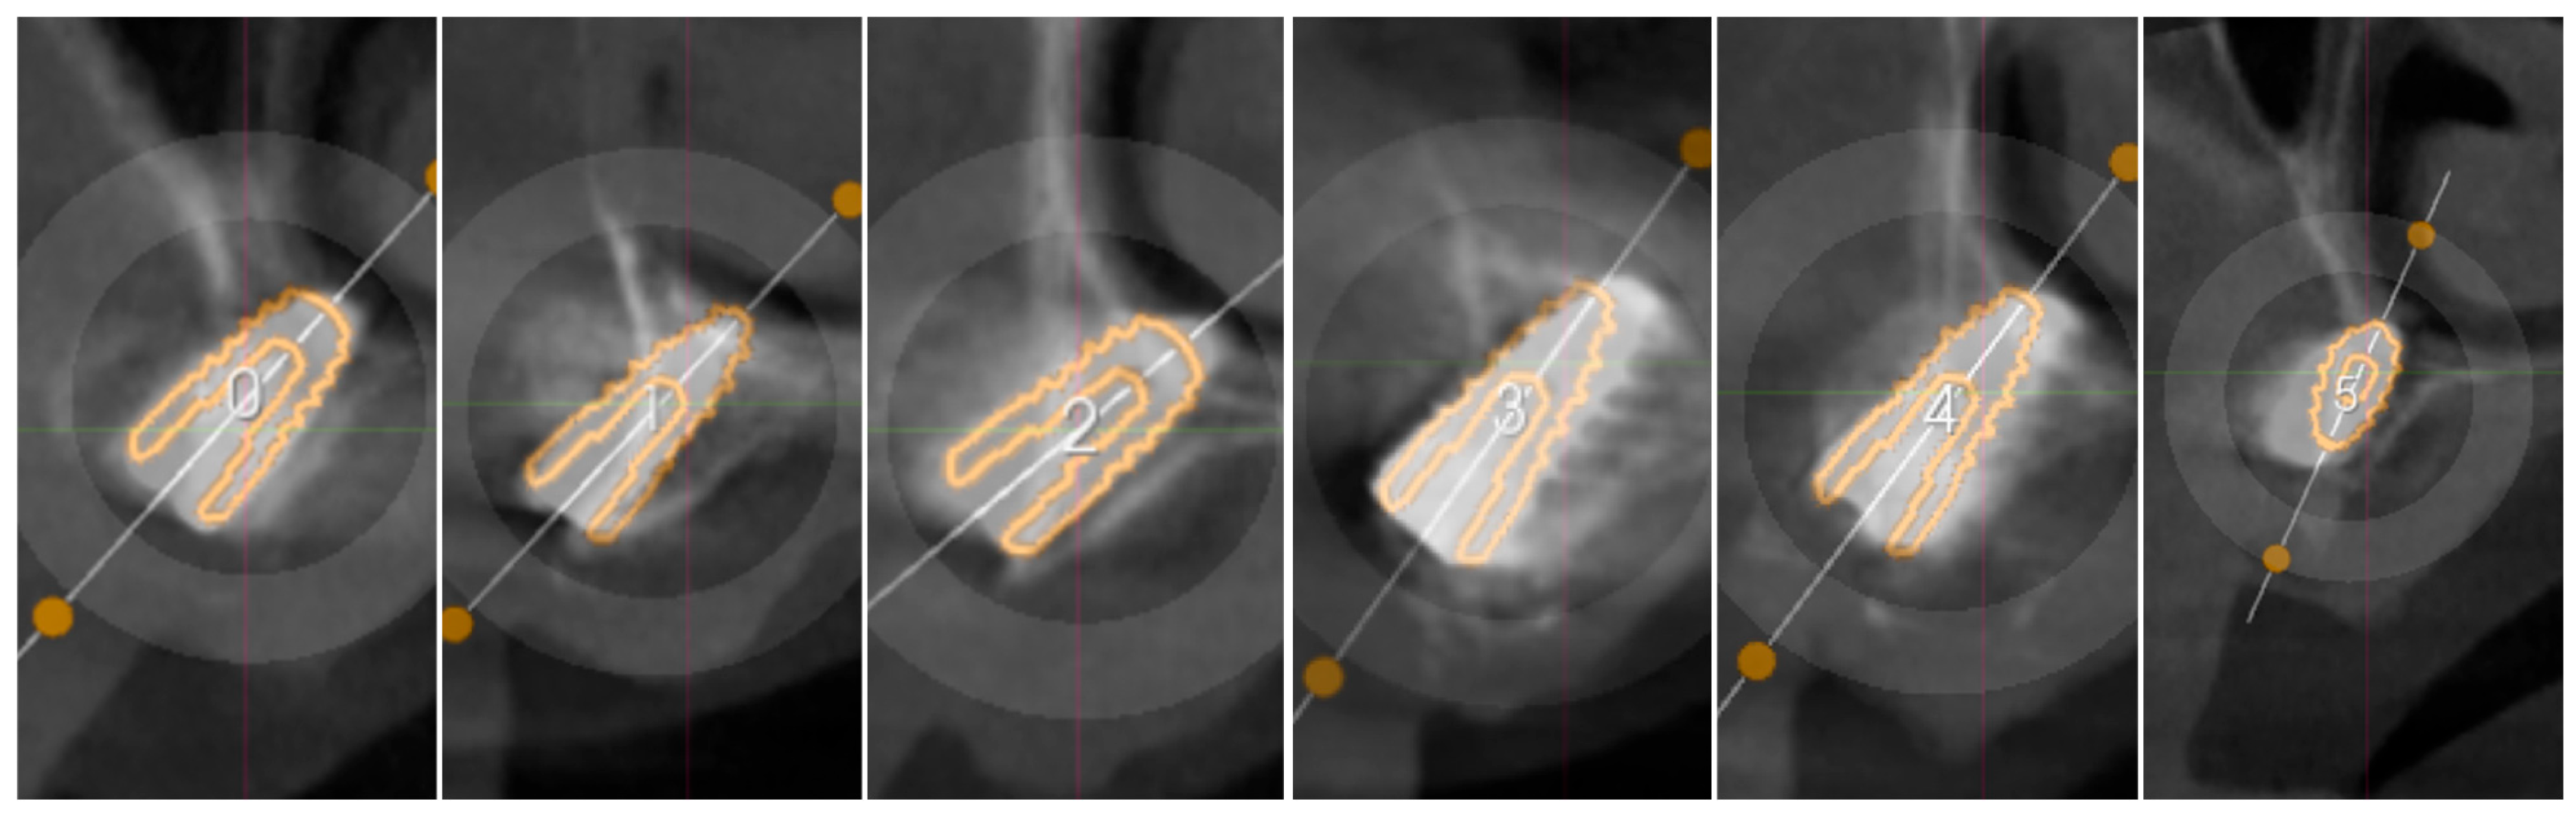

3.2. Surgical Guide Accuracy

| Implant Reference | Palatal-Vestibular Accuracy (From the Apex of the Implant) | Mesio-Distal Accuracy (From the Apex of the Implant) | Height Accuracy (From the Apex of the Implant) |

|---|---|---|---|

| Implant 0 | 0.5 mm | 1 mm | 0.7 mm |

| Implant 1 | 0.3 mm | 0.4 mm | 0.2 mm |

| Implant 2 | 0.3 mm | 0.2 mm | 0.4 mm |

| Implant 3 | 0.9 mm | 1.1 mm | 0.9 mm |

| Implant 4 | 0.7 mm | 1 mm | 0.4 mm |

| Implant 5 | 0.8 mm | 1.2 mm | 0.2 mm |